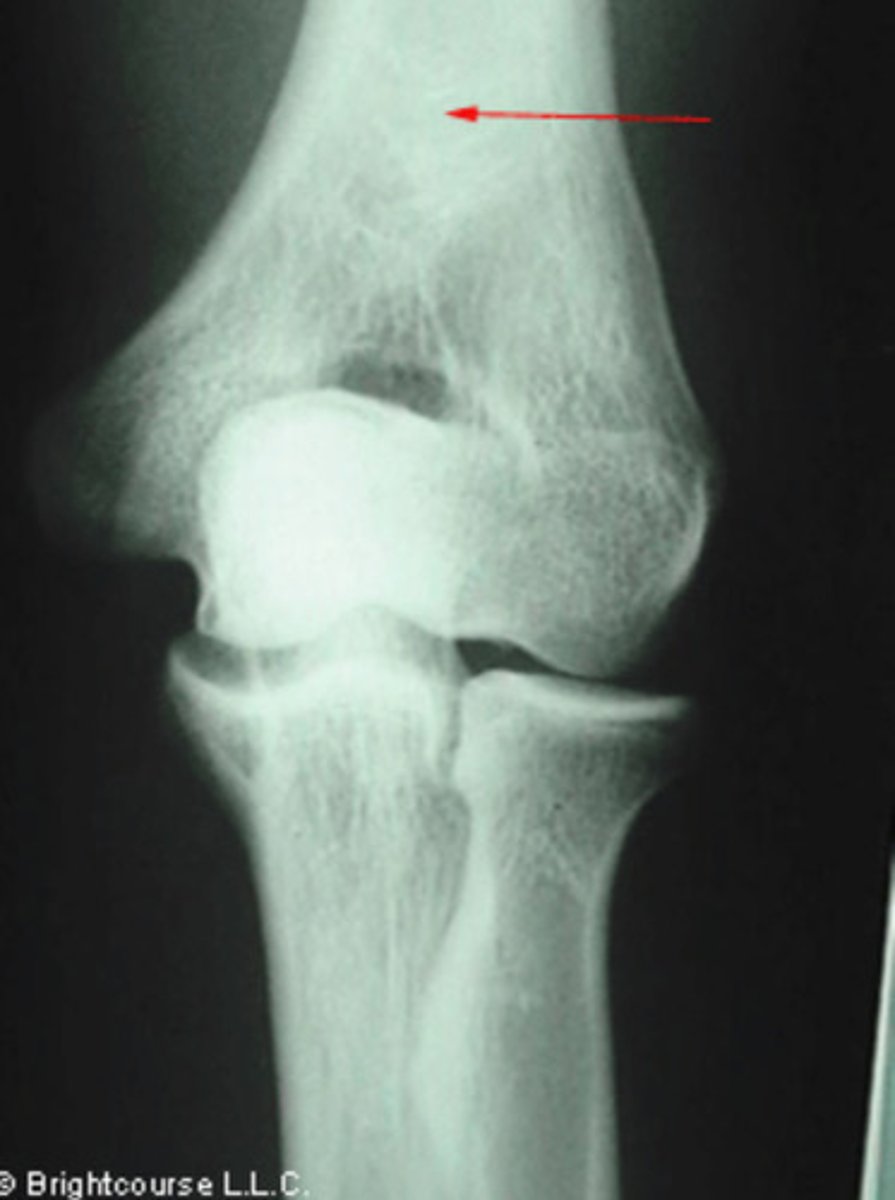

Distal shaft of humerus

What structure is being pointed out by the arrow?